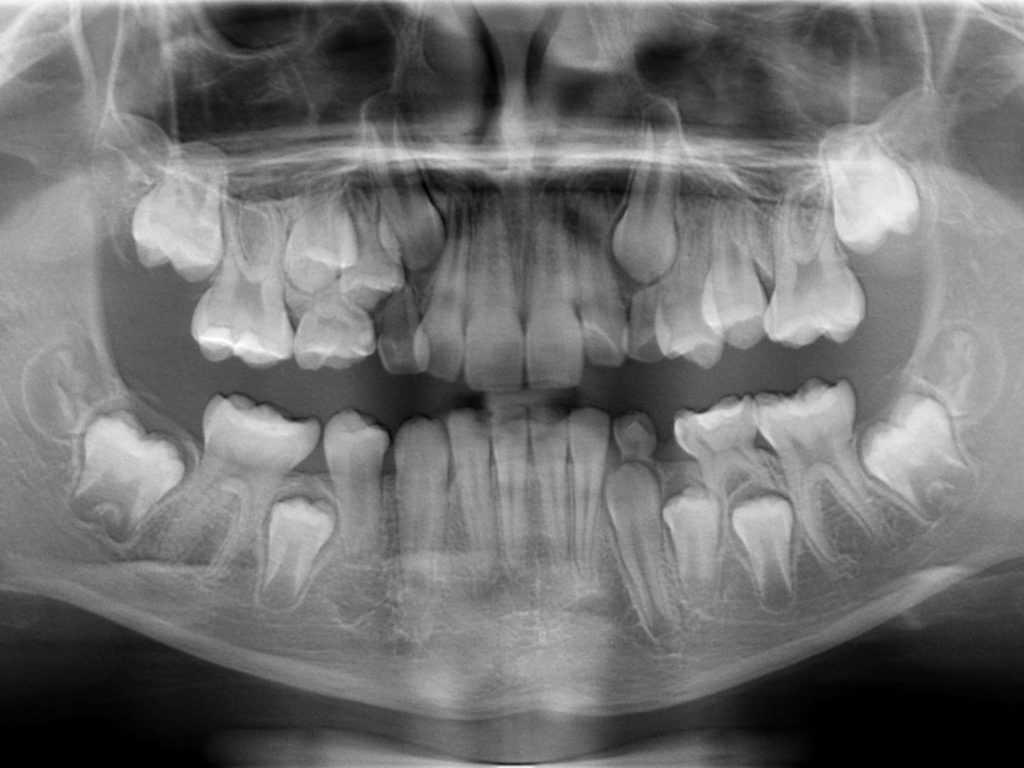

jest szczególnie istotne w przypadkach wrażliwych na promieniowanie, np. przy wykonywaniu zdjęć kontrolnych czy prześwietleń u dzieci.

Stomatologia jak żaden inny dział medycyny na co dzień i powszechnie wykorzystuje badania radiologiczne w procesie diagnostyki i leczenia. W ciągu ostatnich lat w dziedzinie radiologii stomatologicznej doszło do radykalnych zmian i unowocześnień. Konwencjonalną radiologię analogową zastąpiły dużo sprawniejsze i doskonalsze a także przyjazne dla pacjenta ( mniejsza dawka promieniowania) systemy radiografii cyfrowej. Obecnie powszechnie wykonujemy cyfrowe zdjęcia rtg pojedynczych zębów a także cyfrowe zdjęcia panoramiczne i telerentgenogramy. Są one dostępne do obejrzenia i obróbki graficznej w ciągu kilku sekund po wykonaniu badania, a obraz takiego badania można przesłać np. mailem. Najnowszym osiągnięciem radiologii stomatologicznej jest badanie z zastosowaniem tomografii wolumetrycznej CBCT. Badanie to pozwala na doskonałej jakości przestrzenne (3D) obrazowanie struktur twarzoczaszki co pozwala na bardzo precyzyjne postawienie diagnozy, zaplanowanie leczenia i kontrolę jego efektów.

| Zdjęcie panoramiczne | 100 |